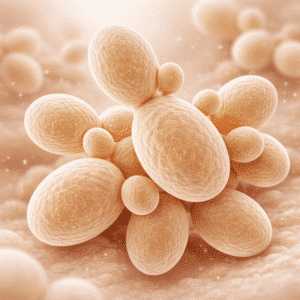

Understanding Candida: Causes, Symptoms, and Smart Ways to Regain Balance

Candida infections can range from mild to life-threatening. Globally, candidemia affects 700,000…